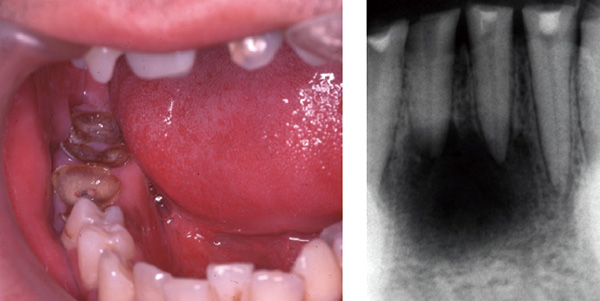

重要なことは薬剤が開始されたら歯を抜かないですむようにしておくことです。抜歯の原因は重度の歯周病、進行したう蝕(根尖病変を有する歯や残根)が主なものです。治療しても治る見込みのない歯、すなわち残しておくだけで顎骨壊死発症の原因となる、いわゆる「悪い歯」は抜歯しておくことです。抜歯となる可能性の低い歯はしっかりと残せるように治療しておきましょう。そして適切な口腔衛生管理ができるように歯科医師や歯科衛生士から指導を受けましょう。

歯肉や口腔粘膜のキズが発症の原因となることもあります。キズの原因は合わない義歯、歯の詰め物・被せ物の鋭縁であることが多く、口腔内の乾燥によりキズのつくリスクが高まります。また、口蓋隆起や下顎隆起といわれる骨が突出した隆起(写真最下段)も硬い食物などでキズがつきやすい状態です。不具合のある義歯や詰め物・被せ物の調整や作り直してもらうことが必要です。口腔粘膜の乾燥については水分摂取・うがいや保湿剤を適用してください。骨隆起についてはリスクを評価し、除去(形成術)の必要性を検討してください。